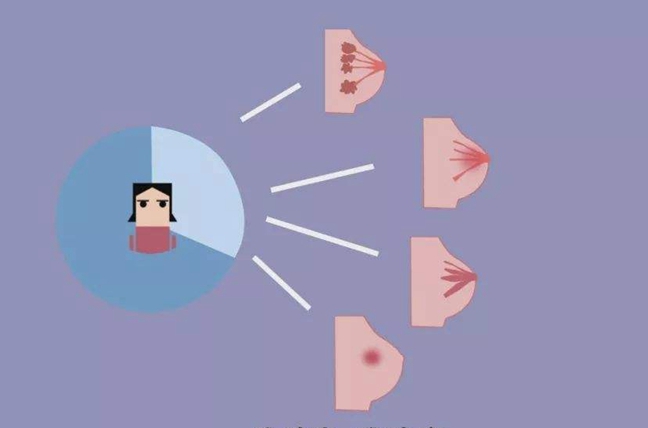

怎麼區分乳腺結節和乳腺增生?

乳腺結節是指醫生在觸診或者超聲看到無法定性的一些結節,乳腺增生是一種症狀。

乳腺結節是指醫生在觸診或者超聲看到無法定性的一些結節,都可以統稱為乳腺結節。乳腺囊性增生、乳腺纖維瘤病變、乳腺導管內乳頭狀瘤還有一些乳腺腫瘤性的結節。乳腺增生是一種症狀,是指人體激素不平衡、內分泌紊亂時在經前産生的經期疼痛,自我觸診的時候感覺乳腺有包塊、腫塊,這樣的一類綜合症狀。